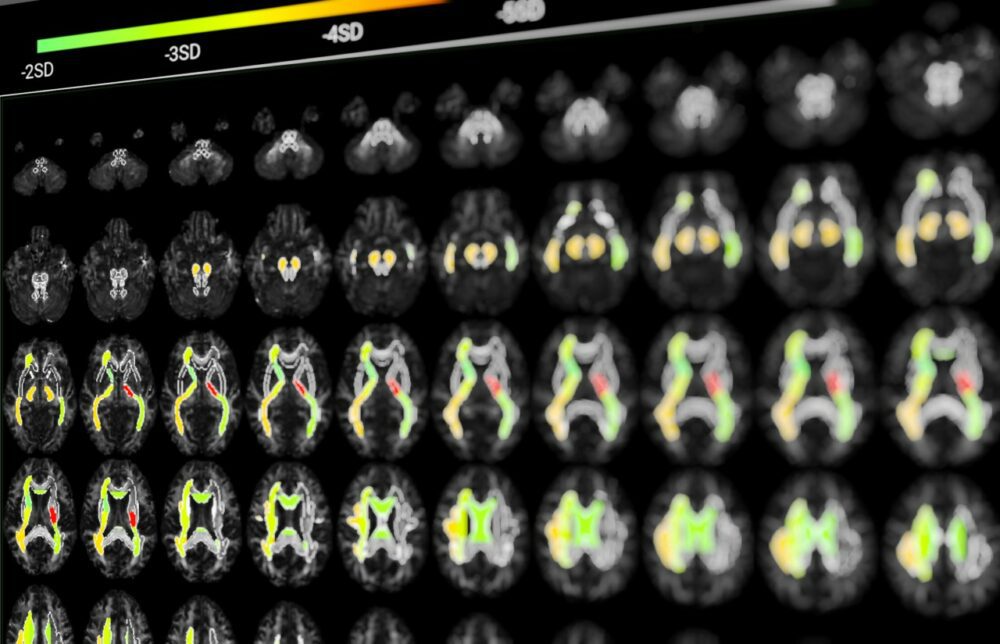

BrainTale’s study represents a significant breakthrough in the differential diagnosis of parkinsonian syndromes, involving a carefully selected cohort of 189 subjects. Among these participants, 92 were diagnosed with Parkinson’s Disease (PD), 45 with Multiple System Atrophy (MSA), and 42 with Progressive Supranuclear Palsy (PSP). Utilizing calibrated diffusion tensor imaging (DTI), BrainTale’s platform analyzed the participants’ brain data to extract diffusion markers, which serve as quantitative indicators of white matter integrity. This advanced MRI technique provides detailed insights into neurodegenerative processes, forming the foundation for an accurate diagnostic model.

The extracted diffusion markers were then analyzed using a supervised learning classification model designed to differentiate between PD, MSA, and PSP based on their unique diffusion profiles. The effectiveness of this model was evaluated through receiver operating characteristic (ROC) curve analysis, a robust method for assessing diagnostic accuracy. The study achieved an impressive average area under the ROC curve (AUC) of 0.87 ± 0.05, indicating high diagnostic performance. Additionally, the model demonstrated an average specificity of 0.74 ± 0.10 and an average sensitivity of 0.90 ± 0.07, reflecting its ability to accurately identify true cases of PD and reduce false positives.

BrainTale specializes in the quantification and standardization of white matter through a software-based medical device solution. This platform offers non-invasive, quality-controlled clinical reports derived from DTI data. By providing objective measures, BrainTale supports the development of new therapies and assists clinicians in making informed decisions. Their technology aims to transform brain care by addressing the growing medical challenges posed by brain diseases.